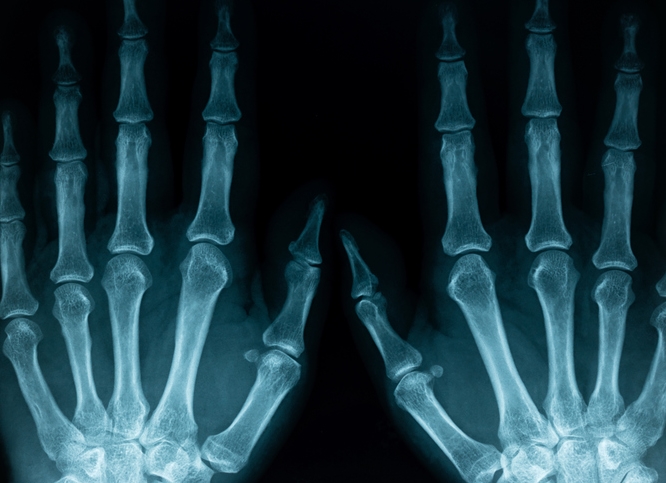

한 달 이상 통증이 지속되거나 관절이 변형되는 경우에는 병원 진료가 필수입니다. 정형외과 또는 류마티스내과에서 엑스레이, 초음파, 혈액검사 등을 통해 원인을 진단합니다. 간혹 통풍, 건선 관절염 같은 복합질환이 발견되기도 하므로 초기 검사가 매우 중요합니다. 전문의 상담을 통해 자신에게 맞는 치료법을 선택하는 것이 회복의 첫걸음입니다.